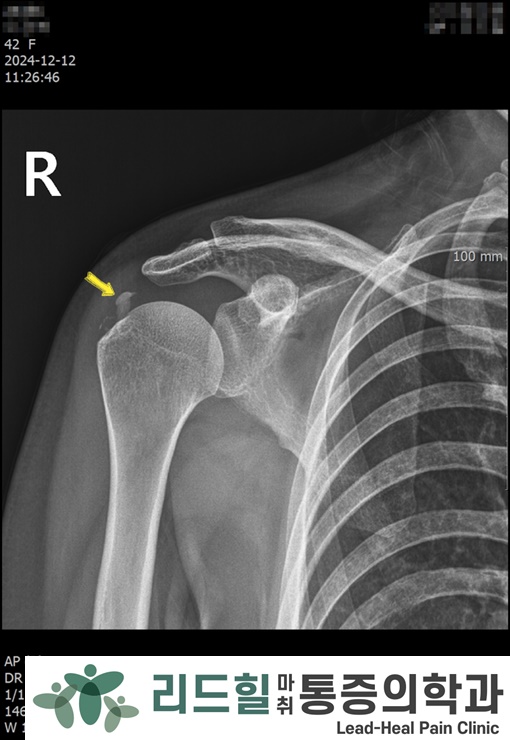

📸 첫 내원 X-ray

우측어깨 (첫번째사진) : 큰 단일 석회

좌측어깨 (두번째사진) : 작은 석회 여러 개

좌측어깨처럼 여러 덩어리가 있으면 시술이 조금 더 까다롭습니다.